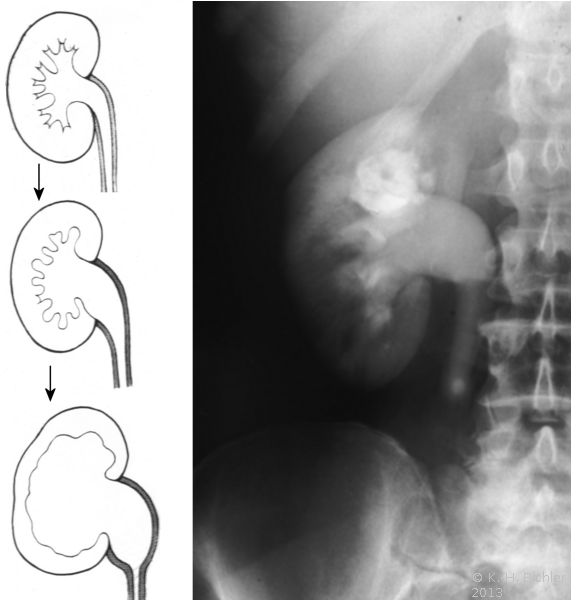

Abflusshindernisse wie Harnleitersteine bzw. Tumoren und anderes können zur Hydronephrose führen. Die Abbildung zeigt den allmählichen hydronephrotischen Umbau der Niere durch Harnstau, z.B. bei Harnleiterstein (Abbildung 24). Der lang anhaltende Aufstau führt zur Erweiterung bzw. dem Wandumbau des Nierenbeckens und Parenchymdefekt.